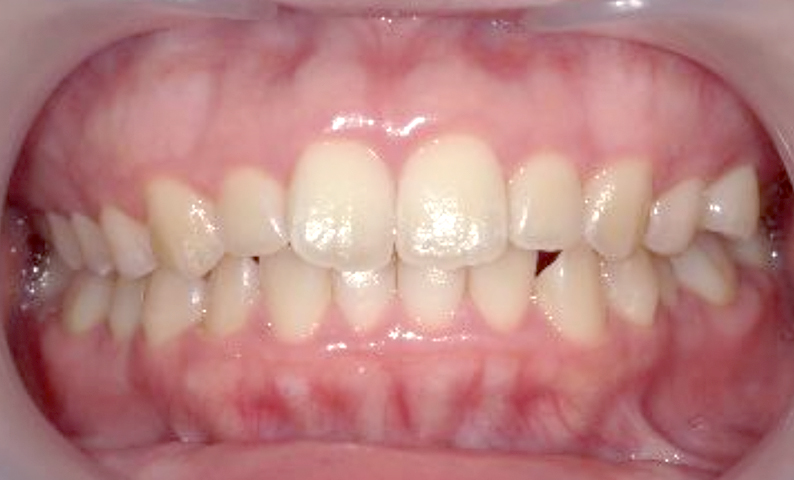

症例_001 前歯「捻転歯」症例

治療期間:6ヶ月金額:48万円+税20代女性少しのねじれ捻転歯下の八重歯

| Before | After |